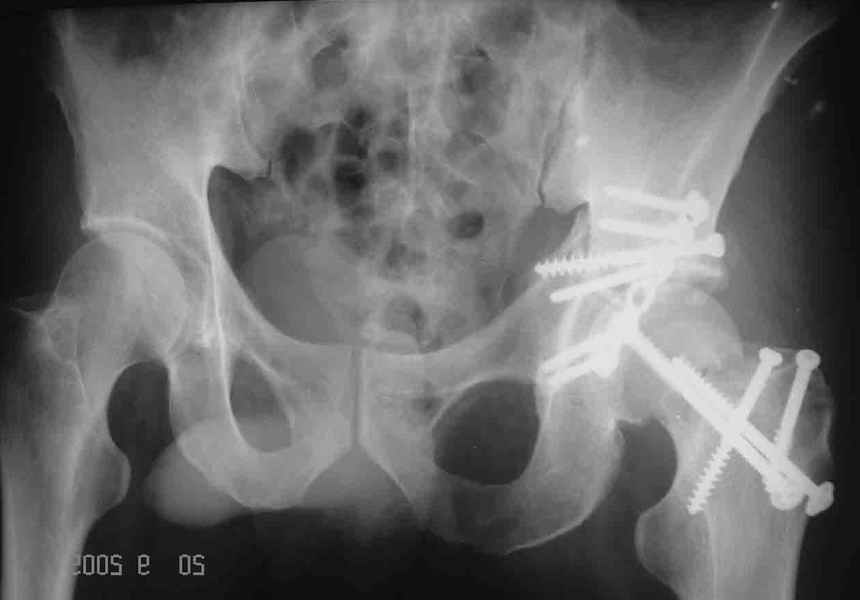

Привет! Вот недавно прооперировали похожий на ваш случай - впадина + шейка (правда у нас впадина поперечный+задний край). После травмы прошло 4 недели. мужчине 46 лет. С такой комбинацией все показания к первичному протезированию. Морально и технически мы к этому уже созрели.Но больной не собрал денег на протез. Выполнили остеосинтез впадины и шейки, прекрасно понимая, что головка вскоре рассосется, мы хотя бы надемся что к этому времени таз срастется, как говорится создали все условия для дальнейшего протезирования (может, и протез в последующем подешевле будет, в смысле, без укрепляющего кольца?). Привет Рункову!